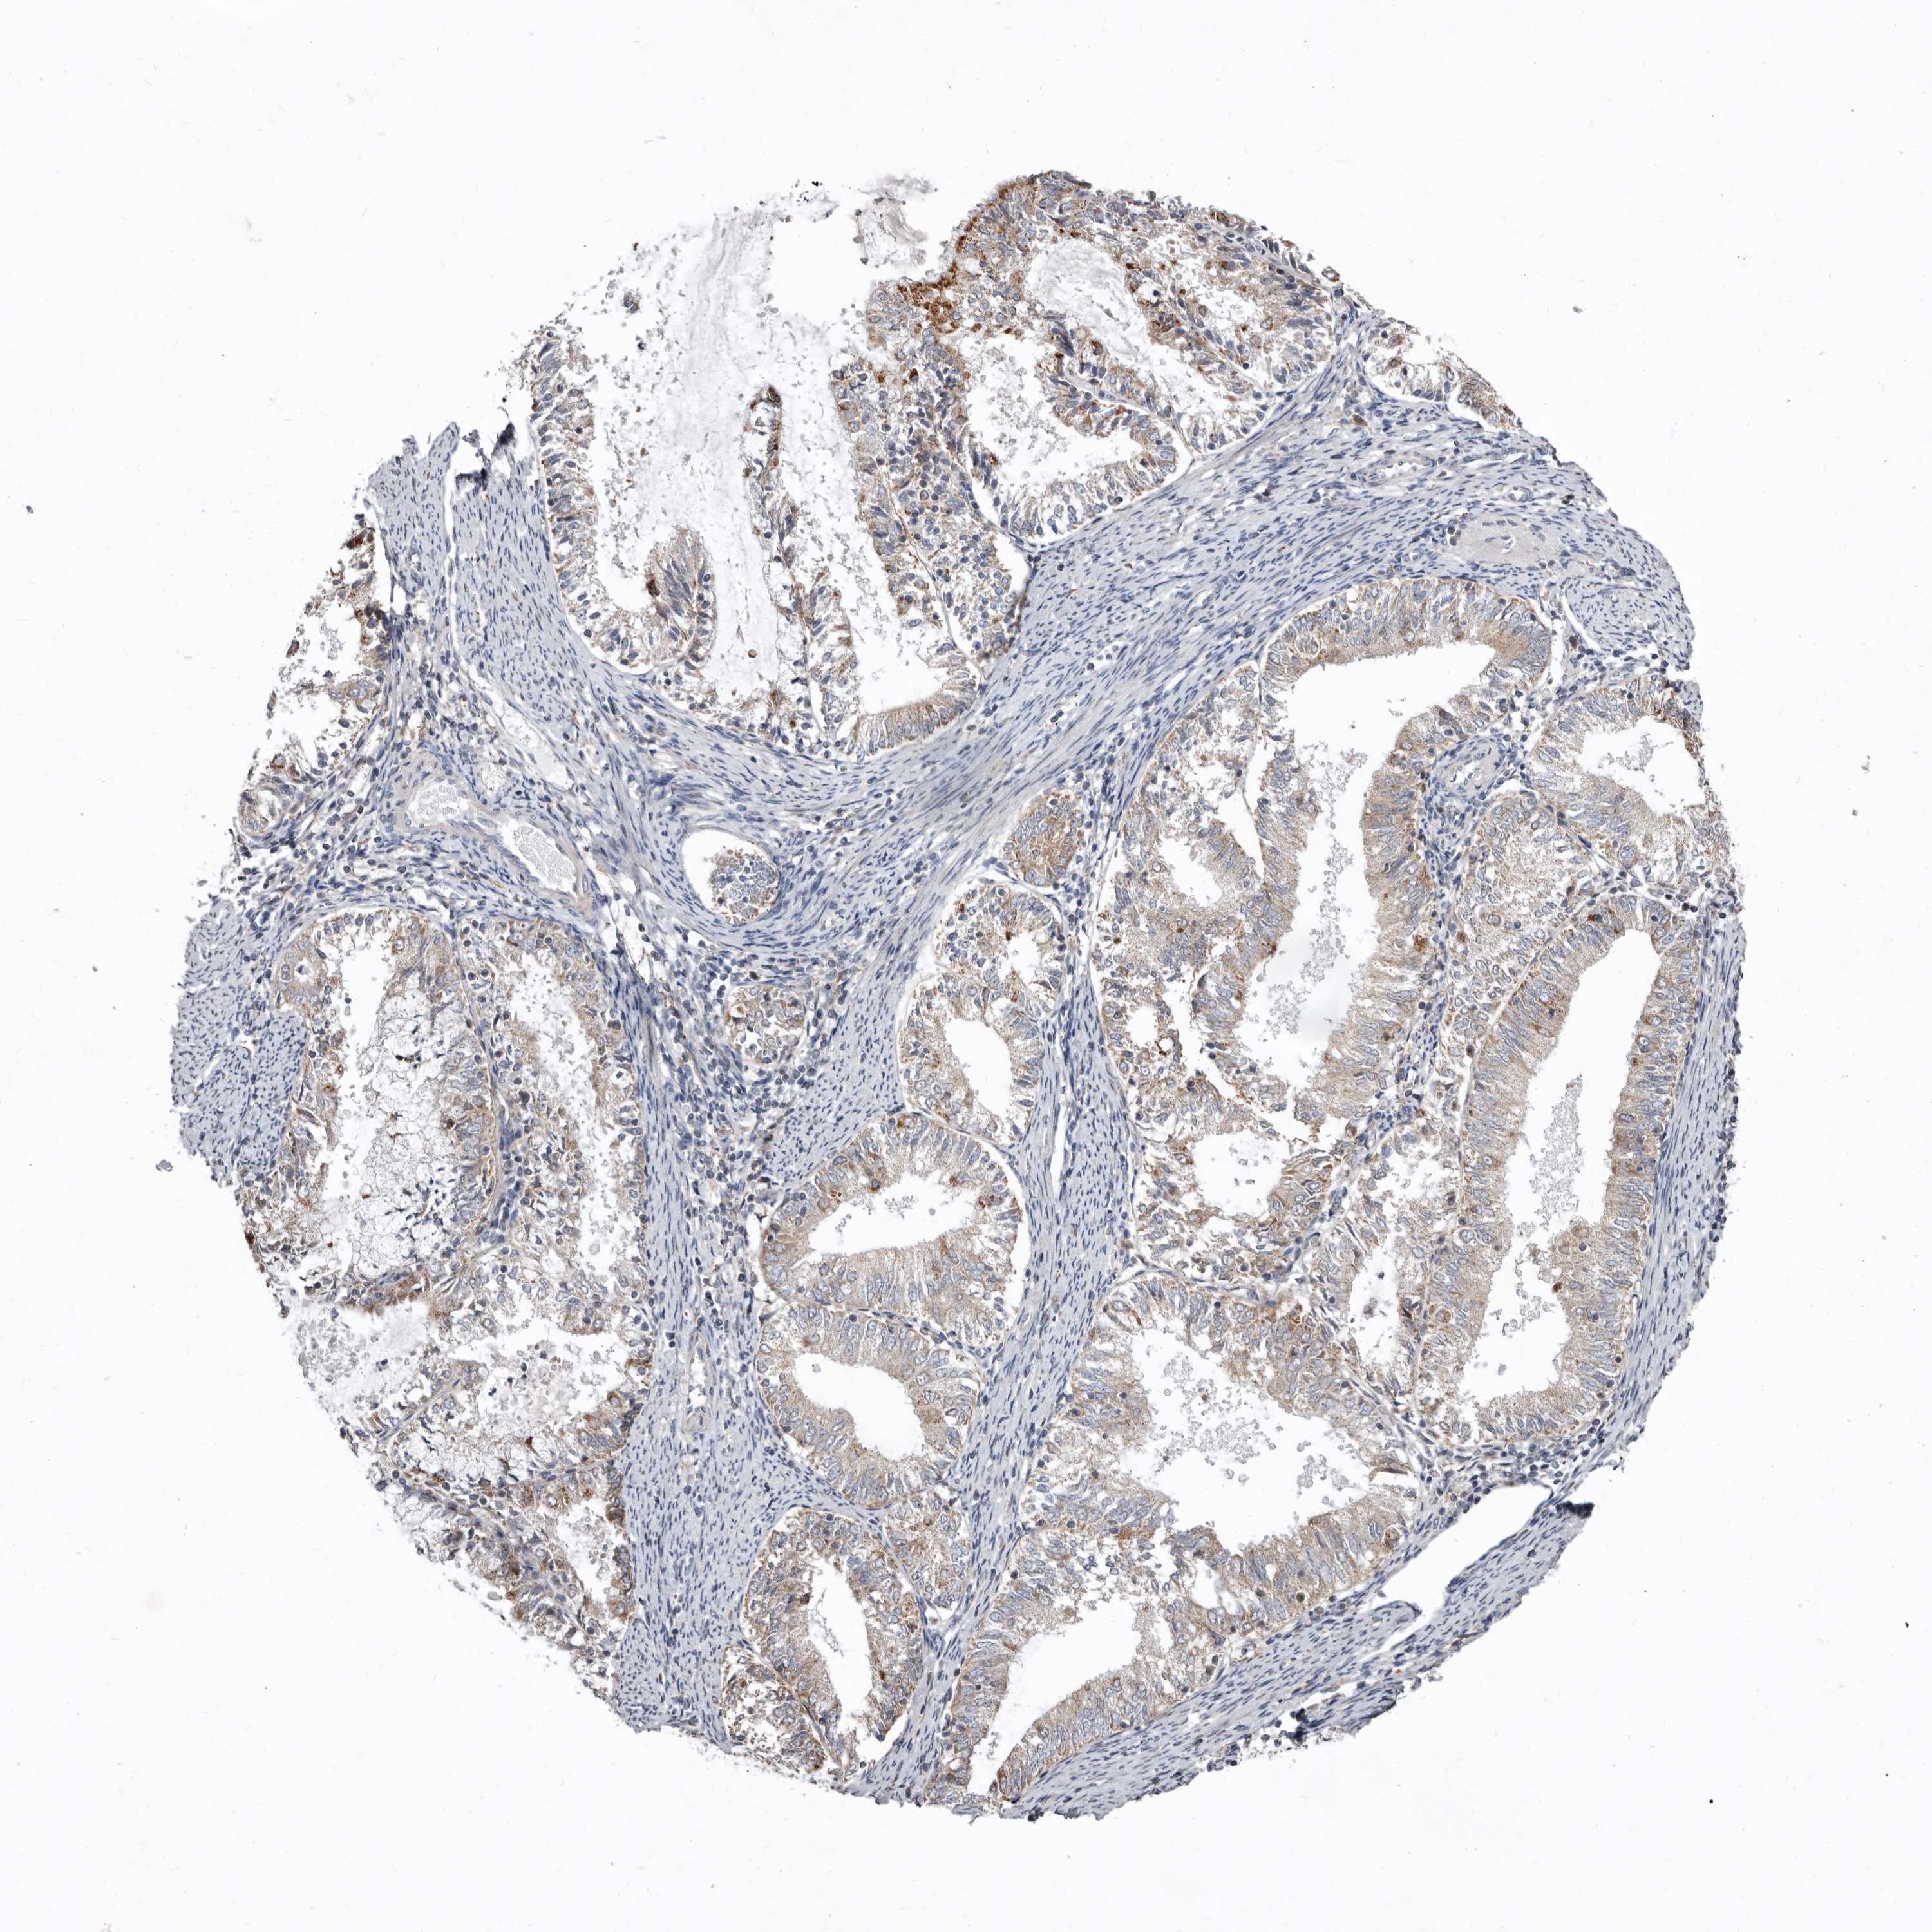

ENDOMETRIAL CANCER - Protein expressioni

A mouse-over function shows sample information and annotation data. Click on an image to view it in a full screen mode. Samples can be filtered based on level of antibody staining by selecting one or several of the following categories: high, medium, low and not detected. The assay and annotation is described here.

Note that samples used for immunohistochemistry by the Human Protein Atlas do not correspond to samples in the TCGA dataset.

Antibody stainingi

Antibody staining in the annotated cell types in the current human tissue is reported as not detected, low, medium, or high, based on conventional immunohistochemistry profiling in selected tissues. This score is based on the combination of the staining intensity and fraction of stained cells.

Each image is clickable and will lead to virtual microscopy that enables deeper exploration of all samples and also displays staining intensity scores, fraction scores and subcellular localization as well as patient and tissue information for each sample.

Antibody HPA029449

Antibody CAB055509

Staining

High

Medium

Low

Not detected

Intensity

Strong

Moderate

Weak

Negative

Quantity

>75%

75%-25%

<25%

None

Location

Nuclear

Cytoplasmic/membranous

Cytoplasmic/membranous,nuclear

Adenocarcinoma, NOS